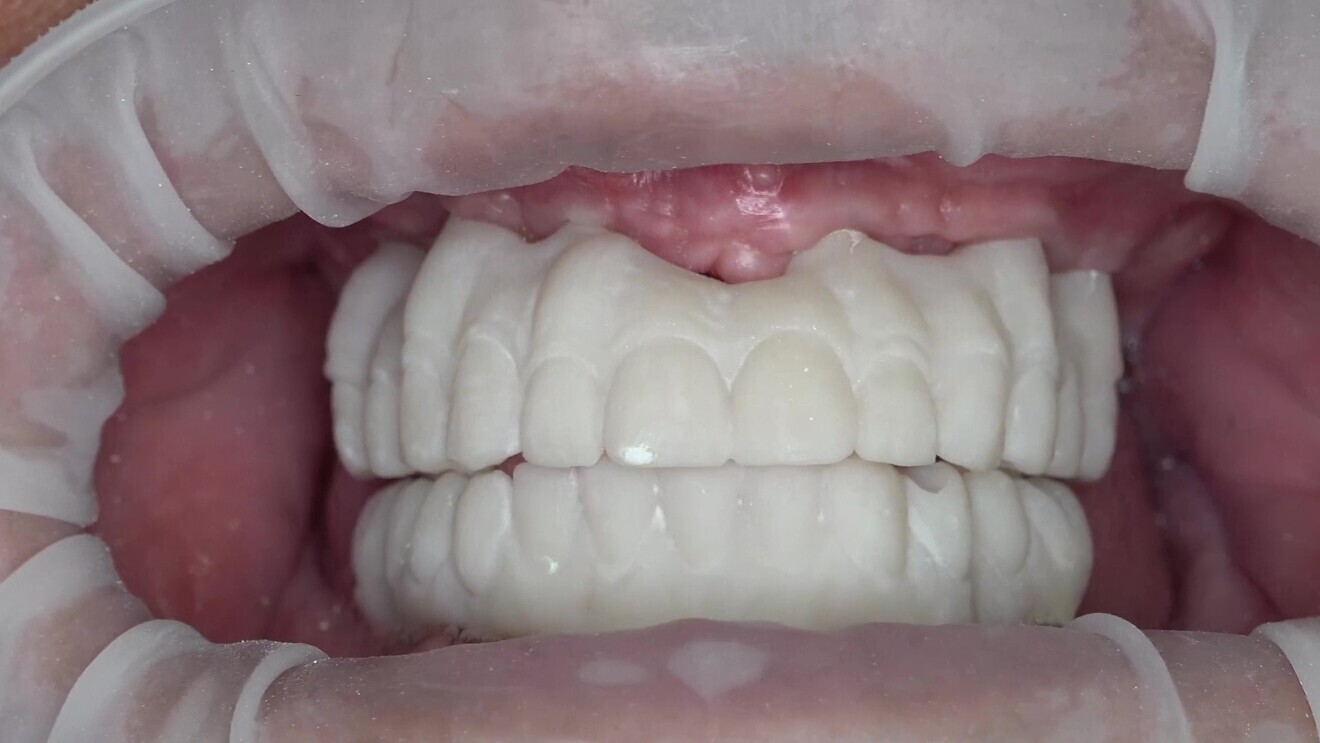

The second set of try-ins was used to check various factors, including aesthetics, occlusion, bite height, hygiene capability, phonetics and function. One important consideration is to avoid using the OptraGate retractor (Ivoclar) when checking the bite. The retractor affects muscular activity and could negatively impact the validation process. These final try-ins closely resembled the final prostheses and were used to make any necessary adjustments before fabricating the final prostheses (Figs. 11 & 12).

Once the validators and try-ins had been successfully checked, the final prostheses were fabricated using the same features and specifications as those of the try-ins. This step ensured that the final prostheses would accurately represent the validated try-ins, providing a comfortable, functional and aesthetically pleasing result for the patient. In this step, it is important to use a material that has the aesthetic features and material properties for manufacture of the full anatomy as a monolithic restoration.11Studies have shown that monolithic zirconia prostheses exhibit high fracture resistance and excellent long-term clinical performance, making them a suitable material choice for full-arch fixed implant-supported prostheses.12 A fully digital workflow requires the user to validate intra-orally and then adjust the initial CAD accordingly and verify that whatever is designed is shown as close as possible in the manufacturing process (Figs. 13 & 14). If the technician has to add veneering material or in any other way change key morphological parts of the restoration, the digital workflow will be less reliable.

Fig. 11: Final try-ins in CAD software.

Fig. 12: The patient wearing the nal try-ins. OptraGate was used to simplify the photography process.